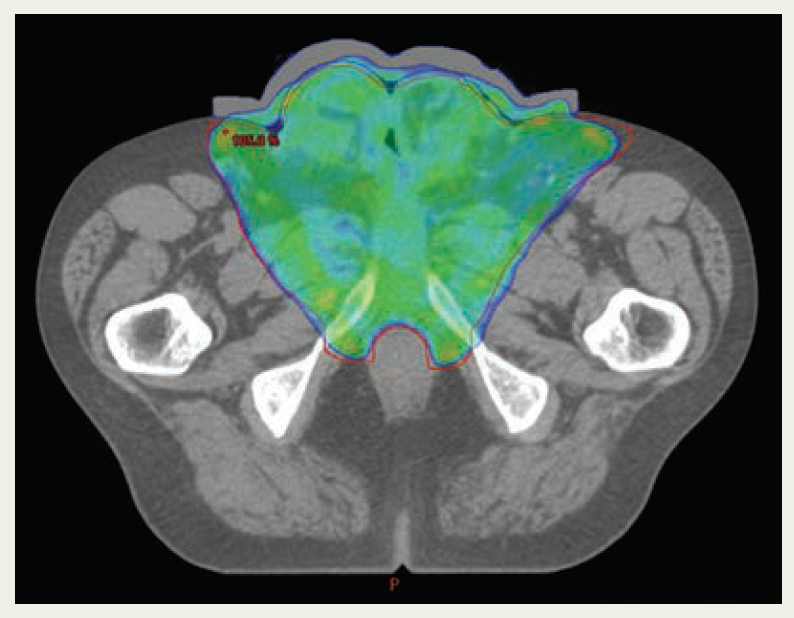

Therefore, treatment was planned with 60 Gy in 30 fractions, with a 6-Gy boost to the primary site using volumetric arc technique, and the use of 1-cm wax bolus covering the gross total volume of the penis and nodes plus margin (Figure 2). MK successfully completed radical radiotherapy with acute grade 2 radiation dermatitis. Initial scans showed a response to treatment, although some of the necrotic residual tumor bed was slow to resolve. The suprapubic catheter was required for ongoing urinary diversion as the tumor shrinkage had essentially resulted in a loss of any normal penile anatomy (Figure 3). Scans continued to show an improvement in the appearance of the tumor bed until there was no discernible remaining cancer. The patient has remained on follow-up for 2 years with no evidence of distant disease or local progression. Of interest, MK developed a transient viral human papillomavirus (HPV) infection in the form of warts at the scrotum 18 months after completing radiotherapy and went on to have HPV immunization.

FIGURE 2. 95% Isodose Coverage With Conformal Volumetric Arc Technique Treatment and Wax Bolus